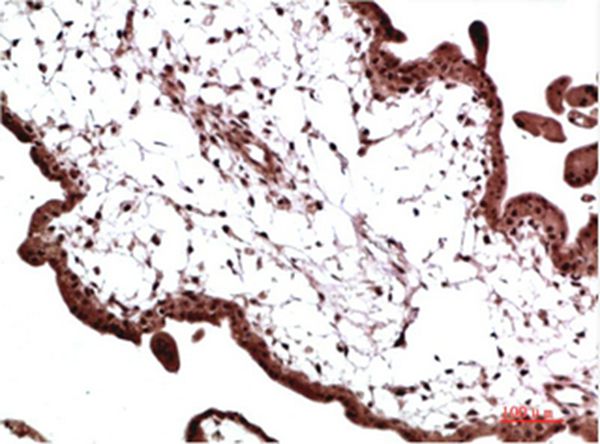

Immunohistochemical analysis of paraffin-embedded Human Placenta Tissue using HP-1γ Mouse mAb diluted at 1:200

Immunohistochemistry: 1:50-1:2000